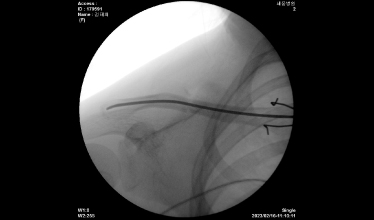

척추 골절

교통사고나 낙상 등에 의한 충격에 척추 골절이 발생하기도 하며, 대부분 고연령층에서 골다공증성 골절로 발생하는 경우가 많습니다.

척추압박골절은 골절 유합은 물론 장기적인 합병증이 발생하지 않도록 주의해야 합니다.

또, 대부분 고령 환자이거나 내과적 기저질환을 앓고 있는 환자로 심각함 골다공증 상태에서 척추 손상이 재발하면 추가적인 골절 위험성이 매우 크므로 골절 치료뿐 아니라 주기적인 골다공증 검사 및 예방으로 환자의 전신상태를 관리해 주는 게 중요합니다.

2021.12.21

2021.12.27